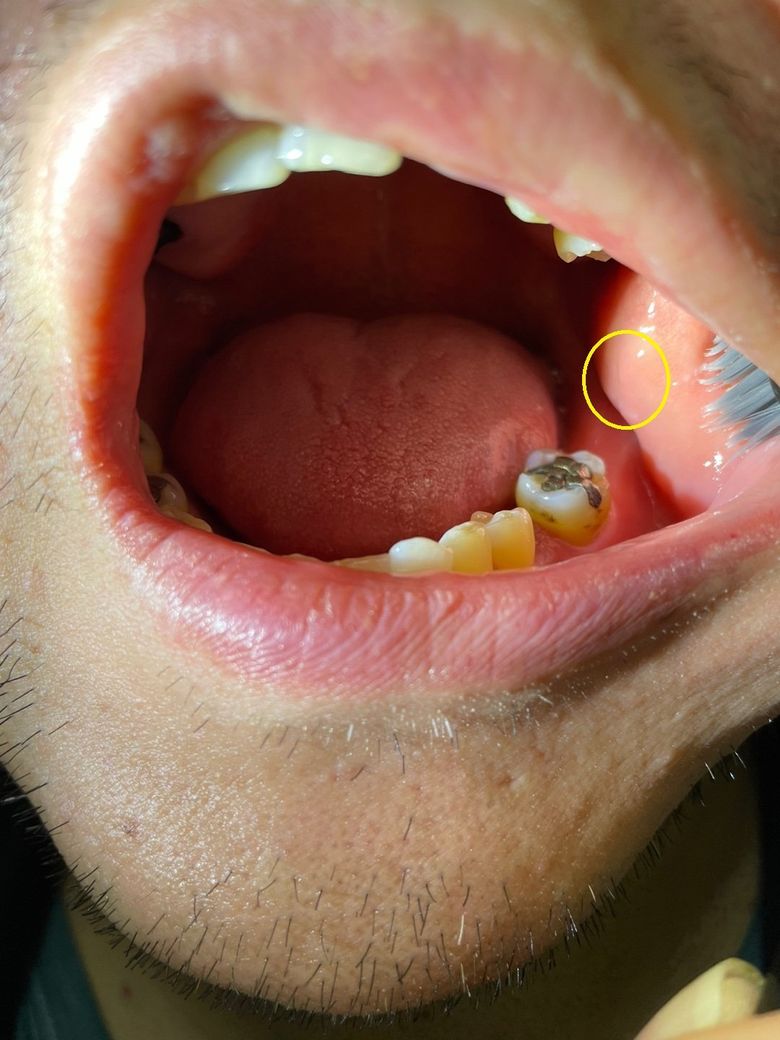

볼점막에 자국이 찢어진 흔적인가요?

제가 몇일전에 입안 사진찍는다고 손으로 졋치고 나서

살짝 안에 찢어진거 같더라구요 그거때문인지 아니면 씹어서 그런건지 모르겠습니다

언듯 모양을 봐선 씹어서 생긴 상처로 보여지는데 맞는건가요?

• 1번 째 사진